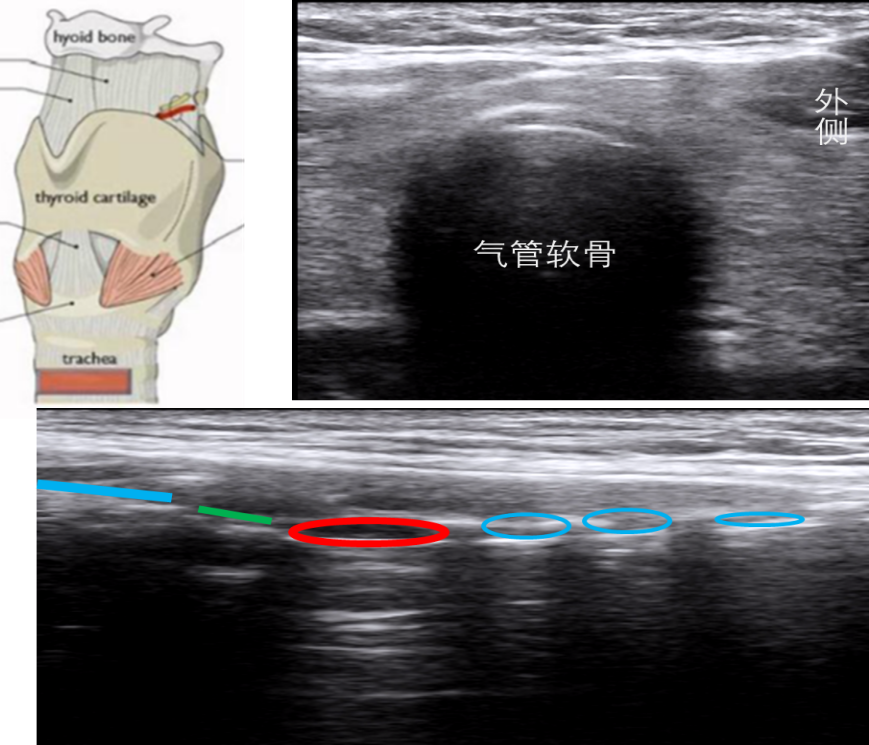

6. 气管软骨平面的扫查

在环状软骨下方即为气管软骨。如果选择高频线阵探头做矢状面扫查,气管软骨为低回声的圆形结构。通常在颈部可以看见6个气管软骨环。气管上组织为皮肤、皮下脂肪、骨骼肌。在2~3软骨环还可以发现甲状腺峡部的存在。此时打开多普勒,可以发现高速颈内动脉的血流。气管软骨环为低回声,矢状面为串珠样存在,横切面为马蹄形(倒U型),由于空气黏膜的存在,会有显著的高回声和后方的伪影。图10右上为气管软骨层面扫查横向切面,图10下为气管软骨平面扫查的矢状面,深蓝色为甲状软骨,绿色为环甲膜,红色为环状软骨,淡蓝色为气管软骨。

图片

图10  气管软骨平面的扫查和切面